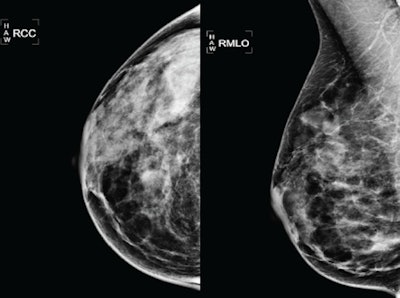

![]() |

| 51-year-old woman: yearly mammogram. All images courtesy of Dr. Saad Ibrahim of Yale University School of Medicine. |